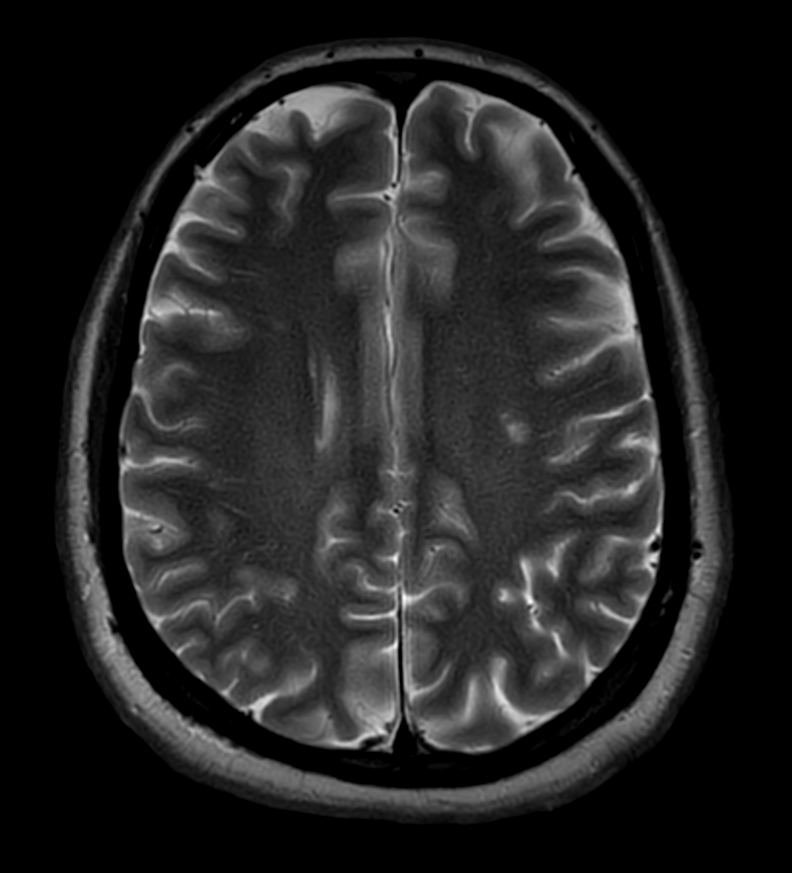

Axial T2w TSE MultiVane XD